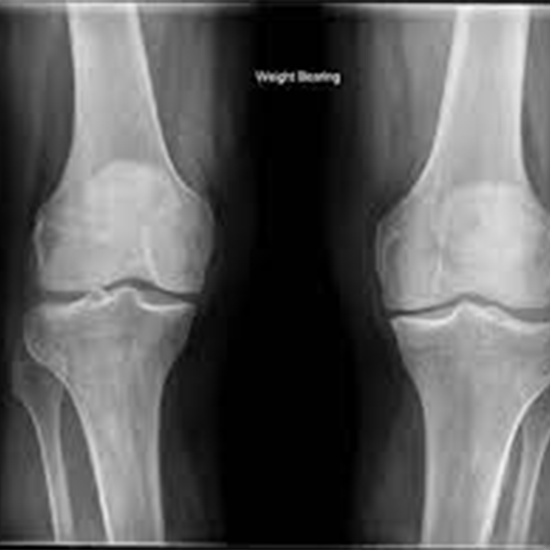

X-ray Both Knee Standing AP & LAT Views

An X-ray of the knee joint can see how well the joint is aligned, how good the bones are, and how much the knee is breaking down.